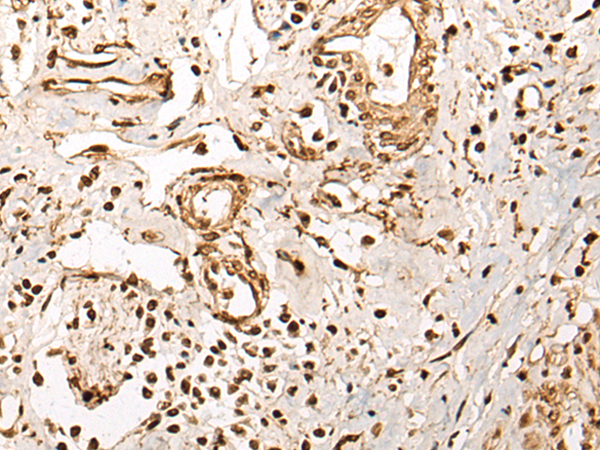

IHC positive control: |

Human thyroid cancer and human cervical cancer |

IHC Recommend dilution: |

25-100 |